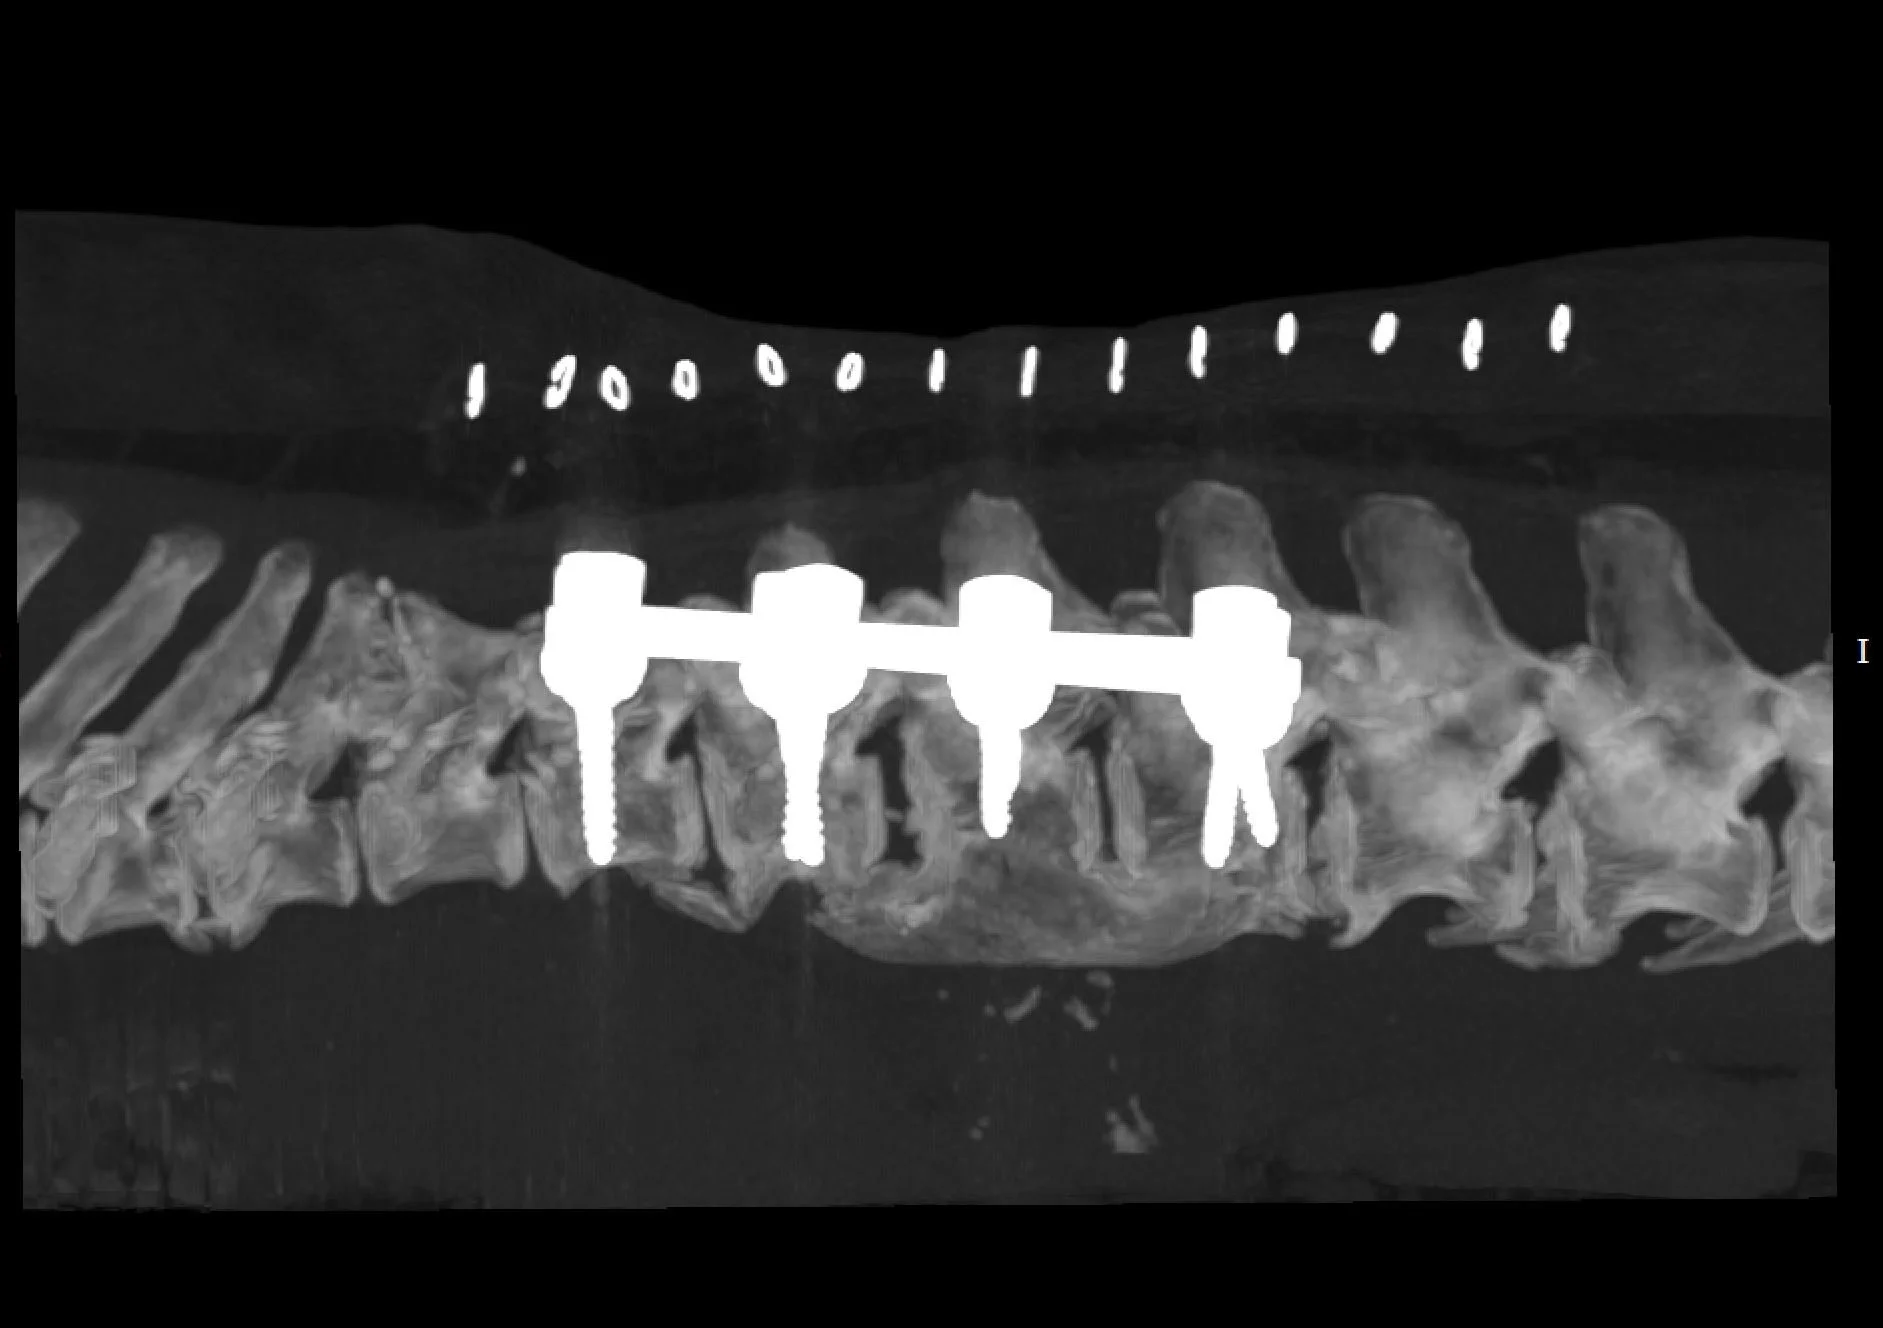

We start with an overview of polyaxial screws and how they are applied to the veterinary vertebral column. We cover fundamental biomechanics of vertebral column stabilization, screw trajectories and choosing the right screw size to build your construct.

The lab portion uses equipment from the Boreal Sciences, Bolt - Mini Polyaxial screw system along with a 3D printed model of a French Bulldog and Pug vertebral column. Participants will apply what they see in lecture to the spinal model.

We will show you the tips and tricks for successful construct engineering and spinal stabilization. From malformations to fractures and everything in-between thoracic, lumbar and lumbosacral stabilization.

This workshop / lab is designed as an introductory and advanced course to the use of polyaxial screws for vertebral column stabilization in dogs and cats. The course is for veterinary neurologists, surgeons and residents in neurology or surgery. The participant will gain knowledge on the fundamental biomechanics of the vertebral column and how to design and use polyaxial screws and rods to create a construct intended to stabilize a portion of the vertebral column. Specifically, the course will cover the thoracic, lumbar and lumbosacral vertebral segments. Attendees will use the laboratory portions of the course to design and build constructs on a 3D printed model of a French Bulldog Vertebral column. Advanced practitioners will use a high thoracic malformation model of a Pug, to engineer and create a construct.